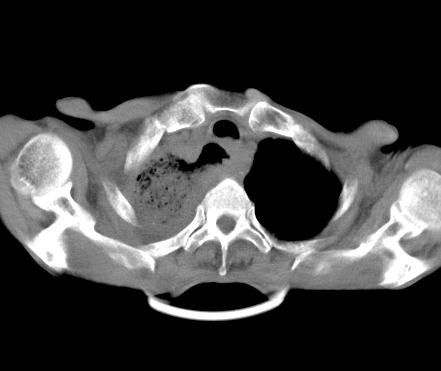

以下是引用gaoshengjiang在2008-5-30 19:53:00的发言:[br]右上叶可见大片实变影,其内可见充气支气管影及囊状影,右上叶尖端支气管走形区可见结节样影,左侧胸腔内可见胸腔胃影。纵隔淋巴结肿大。[br]考虑:1.右上肺阻塞性肺炎伴肺脓肿形成。支持转移所致。[br] 2.左侧胸腔胃。